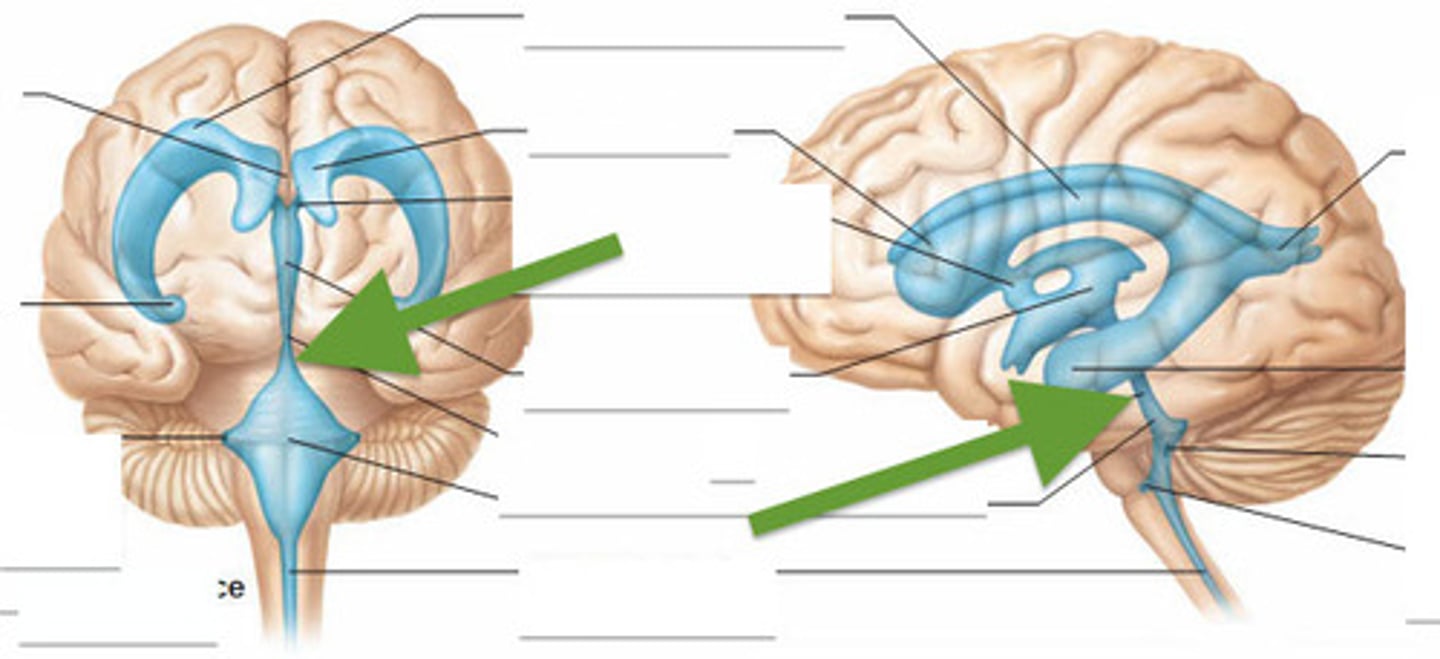

right and left lateral ventricles

third ventricle

fourth ventricle

cerebral aqueduct (mesencephalic aqueduct)

interventricular foramen